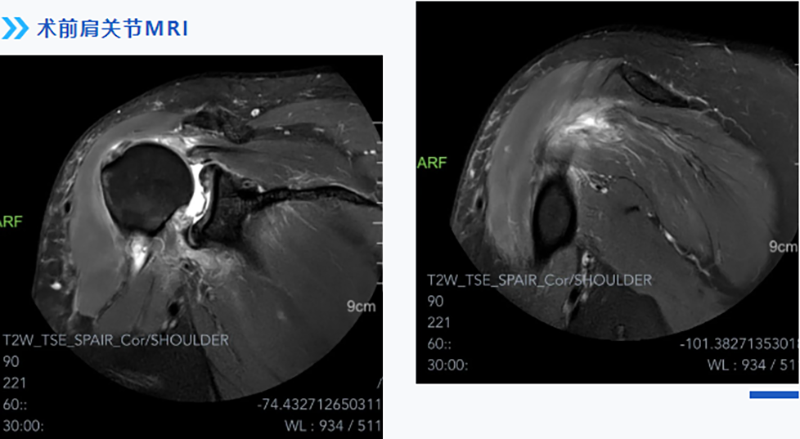

經過多方打聽,張師傅慕名來到柳州市人民醫院運動醫學科就診。運動醫學科主任韋釗嵐博士結合患者實際情況,仔細查體及閱片后給出了明確診斷:巨大肩袖撕裂,腋神經損傷(后上型巨大肩袖撕裂回縮導致神經牽拉)。

醫生介紹,肩袖主要由岡上肌、岡下肌、肩胛下肌及小圓肌組成。巨大肩袖撕裂一般指撕裂直徑大于5cm或撕裂的范圍波及2根以上的肩袖。因為撕裂范圍大,受累肌肉多,無論從手術方案制定還是手術技術難度上均是肩袖手術中最具挑戰的,特別是對多部分軟組織進行組織松解和調節平衡。

考慮到患者對術后功能期望值較高,術中對于如何將撕裂的肌腱完全恢復如初等因素充滿了挑戰。經過充分的術前準備,運動醫學科團隊應用關節鏡下微創技術,根據術中實際情況,精準植入縫合錨釘,將撕裂的肩袖縫合回原本的位置,恢復其原本具有的功能,被牽拉的腋神經也得到了松解,術后患者患肢疼痛、麻木的癥狀立即得到了緩解。